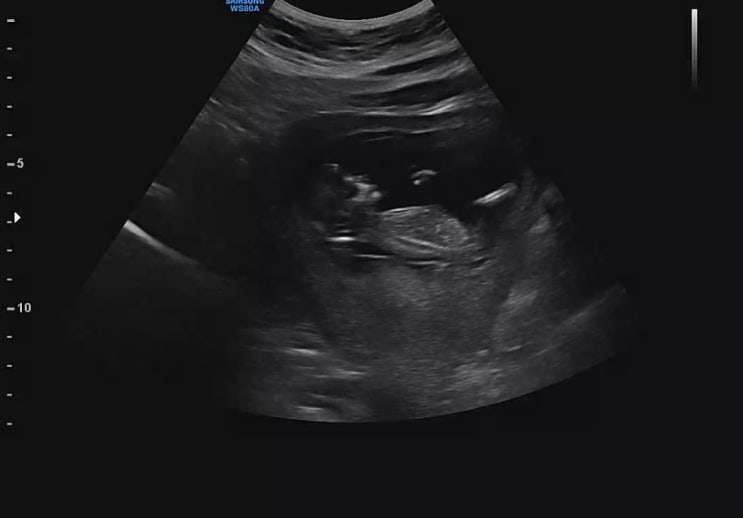

[다낭성 난소 증후군의 자연임신일기 : 26주 검진]입체초음파 + 공포의 임당검사 재검 후기

어느덧 26주 사실 이건 임당 재검 포스팅이다 나는 아무생각없이 26주검진을 갔다 이날 괜히 파워 걱정인형...